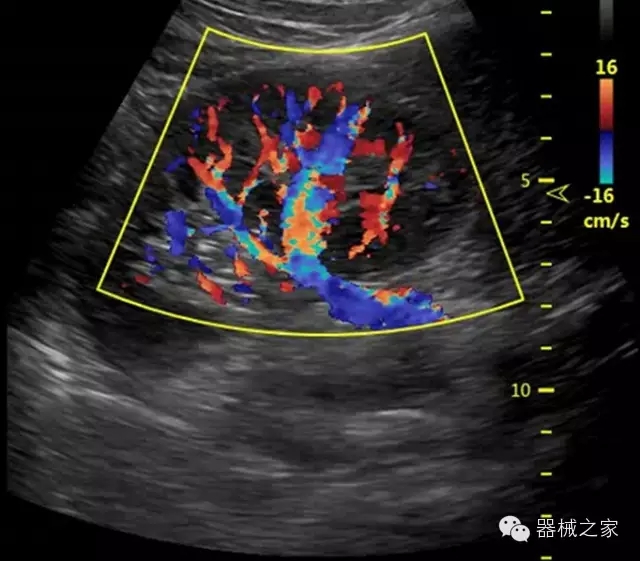

經(jīng)典產(chǎn)品:S8EXP

臨床圖片賞析

產(chǎn)品特點(diǎn)

優(yōu)異的成像技術(shù)

·智能微血流成像技術(shù):智能微血流捕捉技術(shù)可以提取出隱藏在背景噪聲中的弱血流信號(hào),大大提高低速血流的敏感性;

全面的臨床解決方案

·移植S40高端臺(tái)式彩超高端平臺(tái)技術(shù),滿足超聲科腹部、淺表、婦產(chǎn)科、心血管、肌骨等應(yīng)用,提供超聲科完美解決方案;